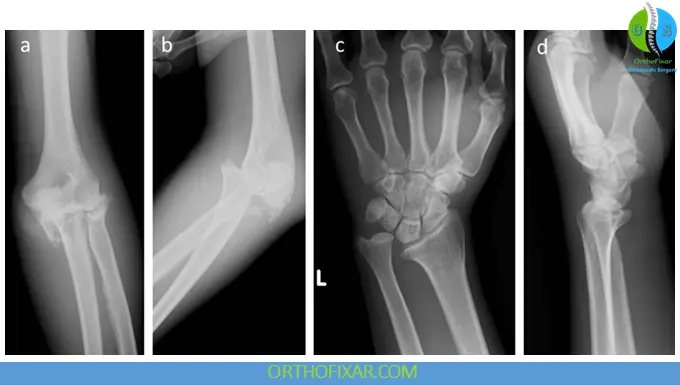

Imaging

- X-ray: radial head fracture ± DRUJ widening

- Ulna variance: increased (suggests proximal radial migration)

- MRI: evaluates interosseous membrane injury

- CT scan: better fracture characterization